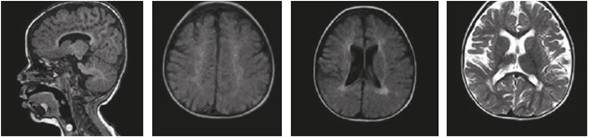

Las imágenes cerebrales, analizadas por un segundo neurorradiólogo, fueron informadas como sugestivas de noxa perinatal de posible origen hipóxico-isquémico; en los controles siguientes no se evidenció progresión de las lesiones, ni aparición de un patrón sugestivo de alguna de las leucodistrofias de origen metabólico (Figuras 1 y 2). La espectroscopia por RMC fue normal (Figura 3).